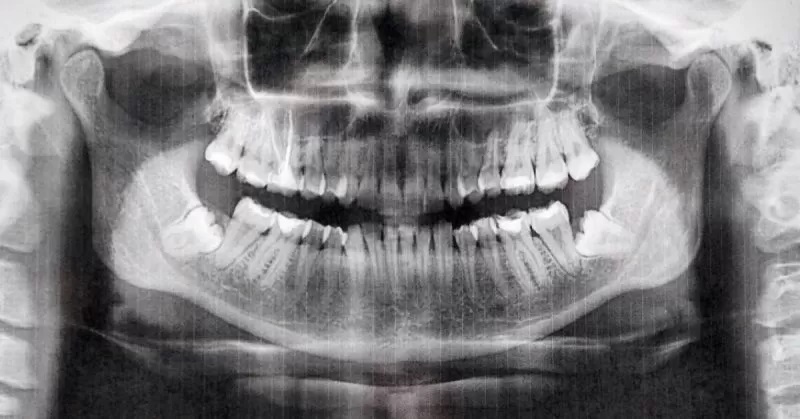

Panoramik merupakan foto gigi dan rahang yang umumnya diperlukan oleh dokter gigi. Panoramic ini dilakukan guna melihat secara jelas masalah kesehatan gigi dan mulut sehingga memudahkan dokter untuk menentukan tindakan yang tepat sesuai dengan kebutuhan pasien dalam meningkatkan kesehatan gigi dan mulut.

Pemeriksaan ini merupakan pemeriksaan penunjang berupa bentuk foto Rontgen untuk mendapatkan gambaran gigi dan jaringan lunak di sekitarnya secara menyeluruh dalam satu kali pemeriksaan. Hasil pemeriksaan menjadi standar dalam merancang terapi atau pengobatan pada pengidap masalah gigi dan mulut. Tak hanya itu, pemeriksaan ini adalah pemeriksaan non-invasif dengan prosedur ekstraoral sederhana yang menggambarkan daerah rahang atas dan rahang bawah dalam satu film.

Tujuan dari pemeriksaan ini adalah untuk melihat lebih jauh dan jelas gambaran gigi dan jaringan lunak yang ada di sekitar rongga mulut sehingga kelainan tumbuh kembang gigi dan rahang seseorang dapat didiagnosis.

Tes ini juga berfungsi untuk mendeteksi kelainan gigi dan mulut, seperti kista di tulang rahang, kanker mulut, tumor rahang, tumbuhnya gigi geraham belakang, kelainan rahang, dan juga sinusitis.